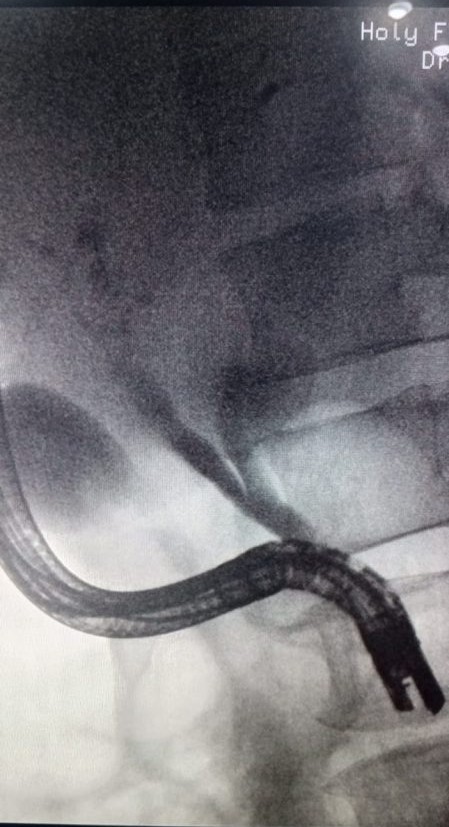

ERCP - Department of Gastroenterology, HFH

ERCP Stenting and Biopsy

ERCP Stenting and Biopsy​